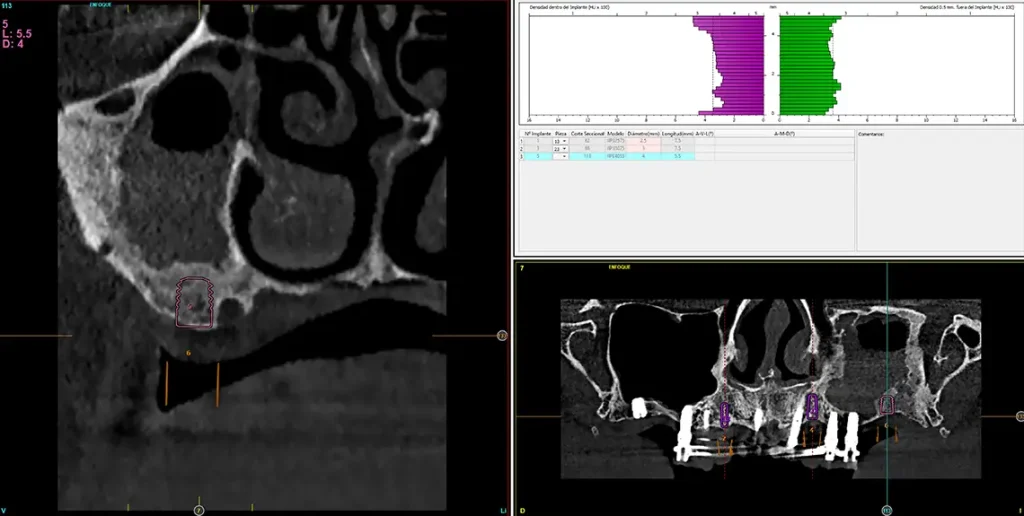

Para realizar una planificación precisa del caso y determinar el volumen óseo residual antes de la cirugía implantológica, se realiza un estudio mediante tomografía de haz cónico (cone-beam) y se visualiza mediante un software específico (BTI-Scan IV). Esta exploración permite medir con exactitud la altura y anchura de la cresta ósea, así como evaluar la densidad de las zonas en las que se prevé colocar los implantes, facilitando así una planificación quirúrgica fiable y ajustada a las necesidades anatómicas del paciente44–47. En las imágenes del cone-beam de control, observamos en el segundo cuadrante una atrofia vertical extrema, con zonas de menos de 4 mm de altura, donde se planifican implantes de 4,5 mm de longitud que serán colocados mediante el procedimiento de elevación transcrestal con fresa de corte frontal y con hueso autólogo obtenido del fresado embebido en PRGF-Endoret como material de injerto. Esta técnica, descrita por nuestro grupo de estudio, nos permite realizar un abordaje seguro del seno maxilar con una escasa invasividad (figs. 8-10)9,25,29,36.

La prótesis se mantiene durante otros cuatro meses, tiempo suficiente para la regeneración de los alveolos de los caninos, donde se planifican nuevos implantes, al igual que en la zona más posterior del segundo cuadrante, donde ahora planificamos un nuevo implante extracorto con elevación de seno transcrestal (figs. 32-34). Estos implantes nos permitirán confeccionar una rehabilitación mucho más eficiente desde el punto de vista de la biomecánica y distribución de ferulizaciones. Una vez insertados, se unen a la carga implantes de la fase anterior generándose un nuevo juego de provisionales (figs. 35-37).

Fig. 34. Imagen de planificación del último implante del segundo cuadrante necesario para terminar la rehabilitación con un buen comportamiento biomecánico.